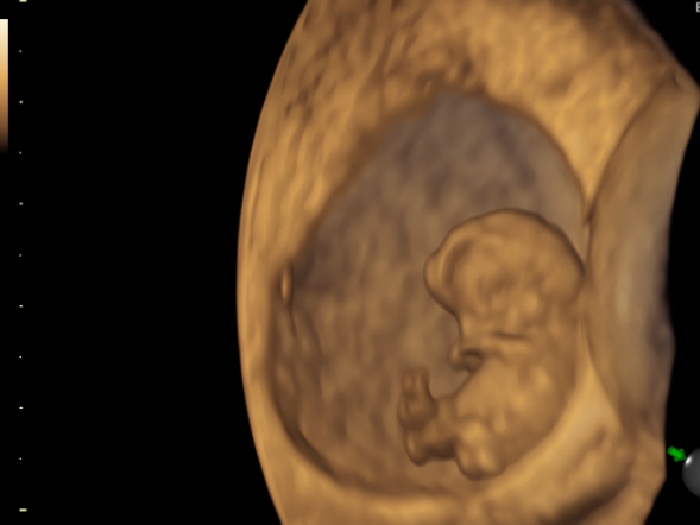

El concepto de manejo multidisciplinario garantiza una aproximación más efectiva en caso de que Usted o su futuro bebé lo requieran y para esto, Fetal Scan cuenta con el apoyo de un grupo selecto de profesionales bajo la coordinación del Dr. Enrique Bermeo P, especialista de amplia trayectoria en Medicina Materno Fetal, ofreciéndole un control prenatal personalizado y protocolizado de acuerdo a las más altas recomendaciones internacionales.